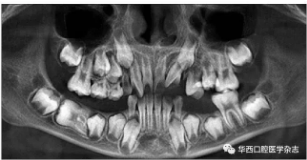

全景片及錐形束CT(cone beam computed tomo-graphy,CBCT)三維重建影像顯示:46牙胚存在,牙冠朝向遠中,且牙長軸與下頜骨下緣接近平行,遠中根發(fā)育約為根長2/3,近中根發(fā)育約為根長1/2且稍向下彎曲,近中根與45牙關系密切,下頜其余牙胚正常(圖2、圖3)。